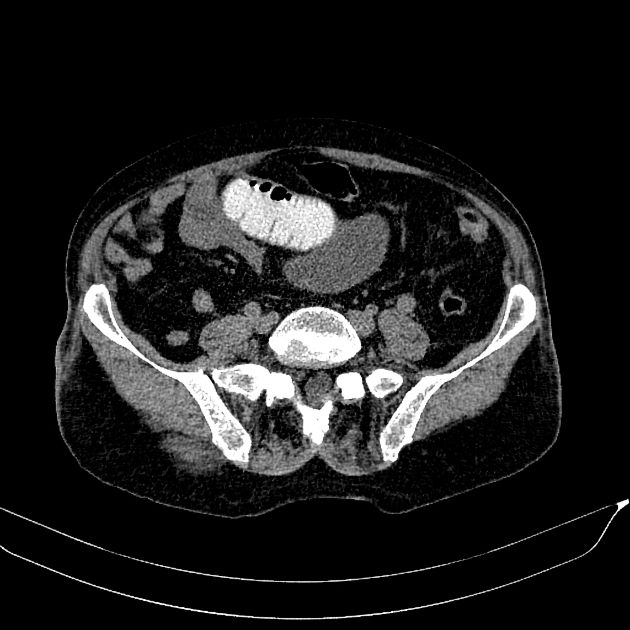

Bezoars

» Thông tin: Nam giới – 80 tuổi.

» Lâm sàng: Đau bụng / Nôn.

# Tắc ruột non do bã thức ăn.